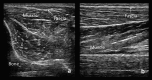

Neuromuscular ultrasound (NMUS) is becoming a standard element in the evaluation of peripheral nerve and muscle disease. When obtained simultaneously to electrodiagnostic studies, it provides dynamic, structural information that can refine a diagnosis or identify a structural etiology. NMUS can improve patient care for those with mononeuropathies, polyneuropathy, motor neuron disease and muscle disorders. In this article, we present a practical guide to the basics of NMUS and its clinical application. Basic ultrasound physics, scanning techniques and clinical applications are reviewed, along with current challenges.